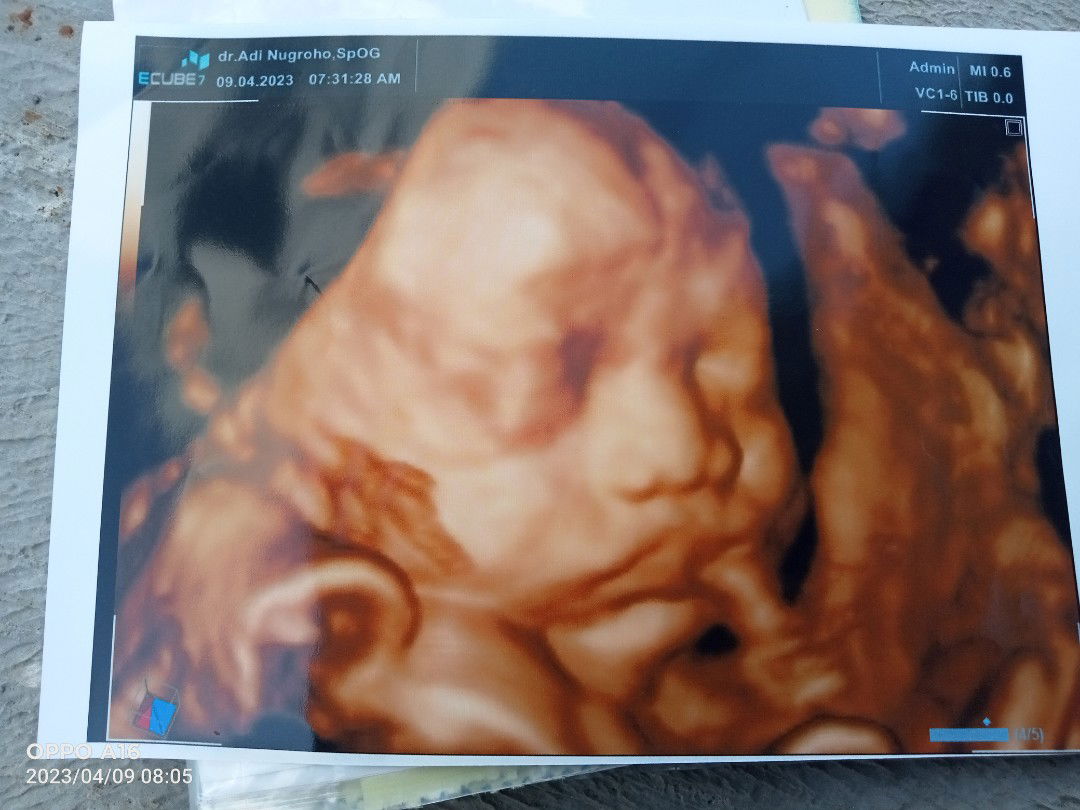

saya pilih tirai 1 krna ini hmil anak pertma smga rejeki utun

tirai 1 karena bru hamil 2 bulan. hehehe.. kali aja rejeki ..

Pilih tirai 2 krna hamil anak ke 2 siapa tau rezeki baby π